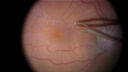

Surgical images showing the peeling of an epiretinal membrane with a 25 gauge forcepts.

Vitrectomy with membrane peelvaatamisi: 428Intraoperative images showing the peeling of an epiretinal membrane - macular pucker - with a 25 gauge forcepts.00000